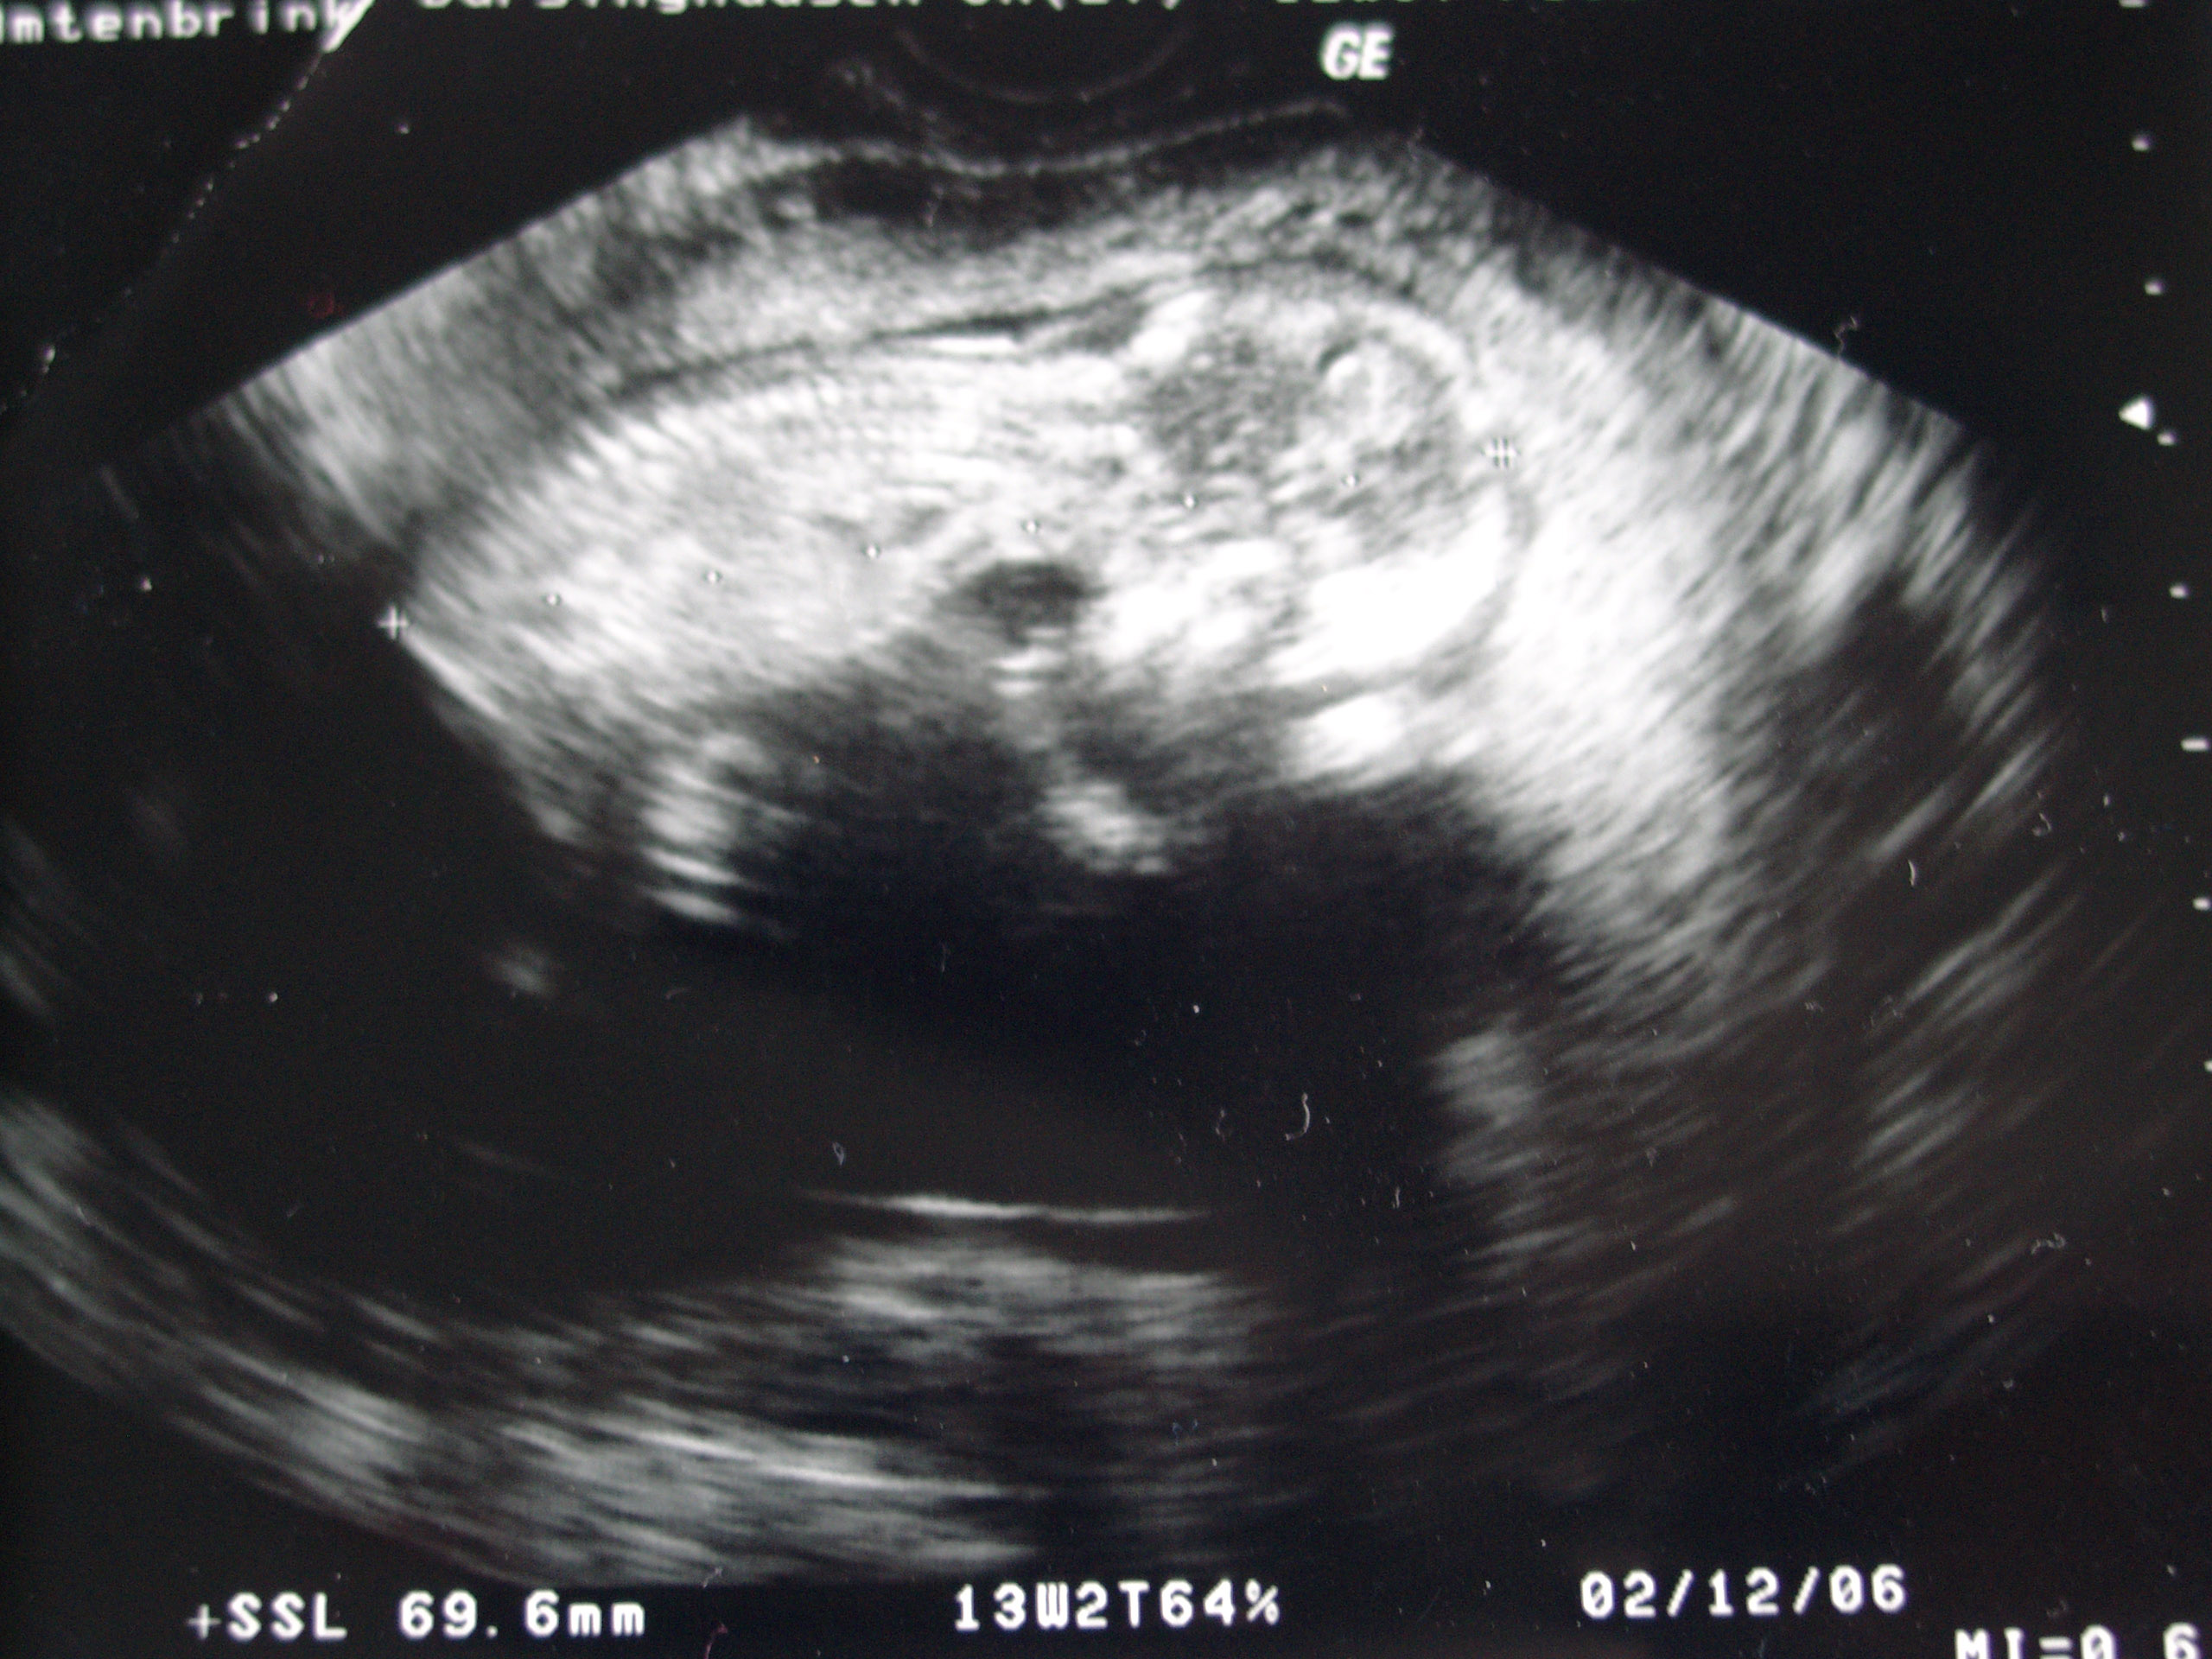

gina, süßes bild! ich finds immer so klasse, dass man jetzt schon genau sieht, dass da ein kleiner mensch heranwächst! na, wenn das kein silvesterbaby wird